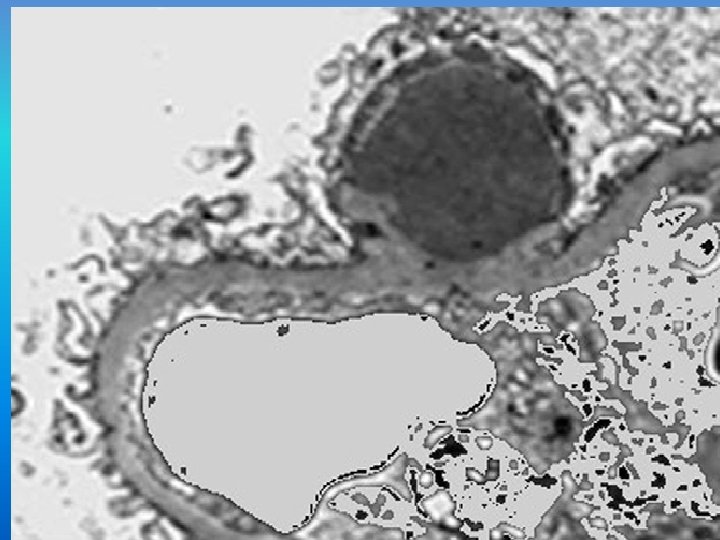

electron microscopy • deposits on the subepithelial side of the GBM (humps) • These deposits disappear after the 6 th week from disease onset. • characteristic lesion is not pathognomonic of APSGN since it may also be found in other immune complex glomerulonephritis, notably lupus nephritis.